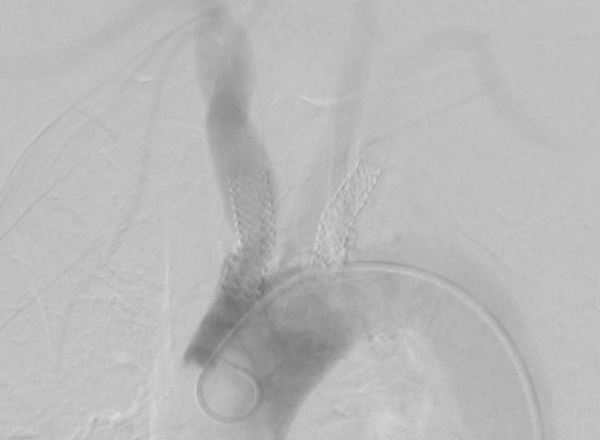

Considering the patient's comorbidities, an endovascular approach was the safest approach. Dual access was achieved using a 6F sheath in the right radial artery and another 6F sheath in the right femoral artery; an aortogram was then conducted showing severe stenosis in the right innominate artery (Figure 1). A carotid angiogram was performed, revealing a vessel size measuring 6 to 7 mm. We advanced a BareWire guidewire (Abbott Cardiovascular) and proceeded with the successful deployment of an Emboshield NAV6 filter (Abbott Cardiovascular) in the right ICA through the radial access as it was the only route for delivering it to prevent entrapment of the filter if placed from the femoral route (Figure 2).